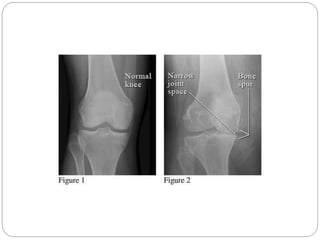

Weight-bearing radiograph is recommended. Radiographs show

joint-space narrowing, subchondral bony sclerosis, cystic changes,

and hypertrophic osteophyte formation.

 Natural history of OA: Progressive cartilage loss,

subchondral thickening, marginal osteophytes

OSTEOARTHRITIS Weight-bearing radiograph isrecommended. Radiographs show joint-space narrowing, subchondral bony sclerosis, cystic changes, and hypertrophic osteophyte formation.